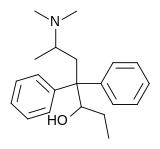

The first fully synthetic opioid was meperidine (later demerol), found serendipitously by German chemist Otto Eisleb (or Eislib) at IG Farben in 1932.[228] Meperidine was the first opiate to have a structure unrelated to morphine, but with opiate-like properties.[199] Its analgesic effects were discovered by Otto Schaumann in 1939.[228] Gustav Ehrhart and Max Bockmühl, also at IG Farben, built on the work of Eisleb and Schaumann. They developed "Hoechst 10820" (later methadone) around 1937.[230] In 1959 the Belgian physician Paul Janssen developed fentanyl, a synthetic drug with 30 to 50 times the potency of heroin.[211][231] Nearly 150 synthetic opioids are now known.[228]